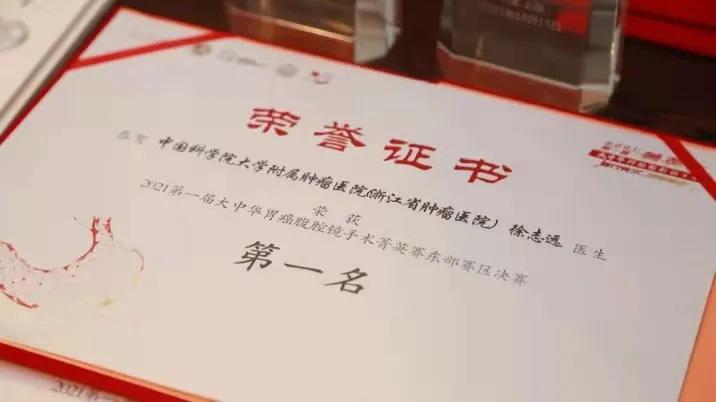

肿瘤中心副主任曾林涓主任医师介绍,“根据病理特征,该患者的肿瘤组织免疫组化染色HER-2(+++),这意味着,她适合曲妥珠单抗靶向治疗联合化疗。在多学科讨论,全面评估患者病情后,我们制订了个体化的精准治疗方案。”

阿英先接受了6个疗程的靶向联合化疗,肝脏转移瘤明显减少、变小。因患者身体较弱,不适合继续强化疗方案,医生调整了治疗方案,她从第7疗程开始进行靶向药物加口服化疗药物治疗,半年后,她的肝脏转移瘤竟完全消失了。

随后,阿英在医生指导下,规律地进行靶向治疗、小剂量化疗和定期营养支持治疗,至今已有20个月,远远超过晚期胃癌13个月的平均生存期,每三个月一次的复查均显示肝脏肿瘤消失,胃镜检查未见明显异常。